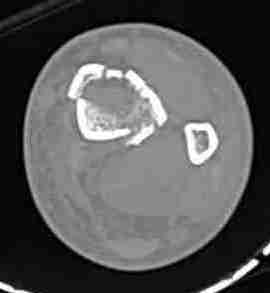

КТ пилона имеем.